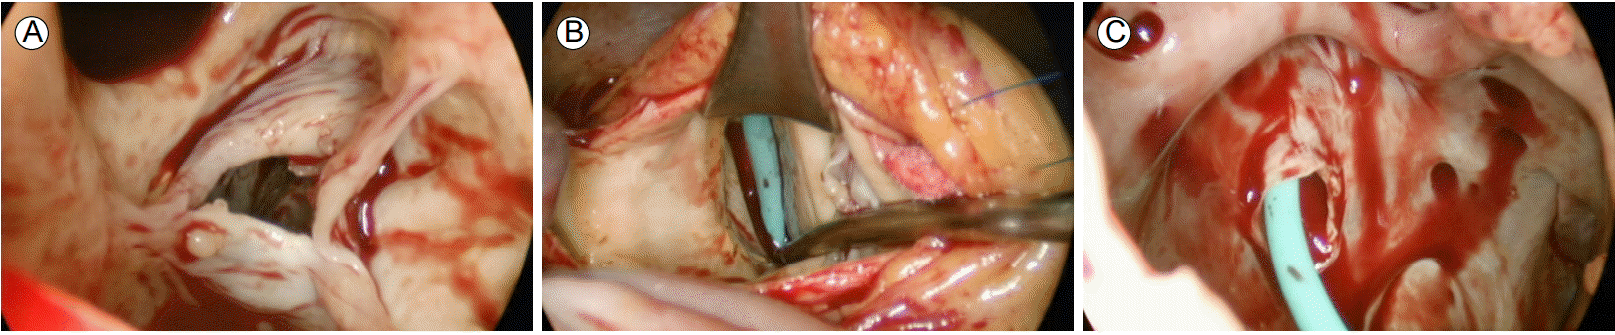

Figure 2.

Transesophageal echocardiography revealed (A) RA enlargement and aorta-right atrial tunnel (arrow). (B) The presence of extra-cardiac blood flow (arrow) between the AO and the RA. (C) A channel originating from the left valsalva sinus of the aorta (arrow). (D) 1.01 cm × 0.67 cm sized vegetations (arrow) in the mitral valve. RA, right atrium; AO, aorta; LA, left atrium; LV, left ventricle.